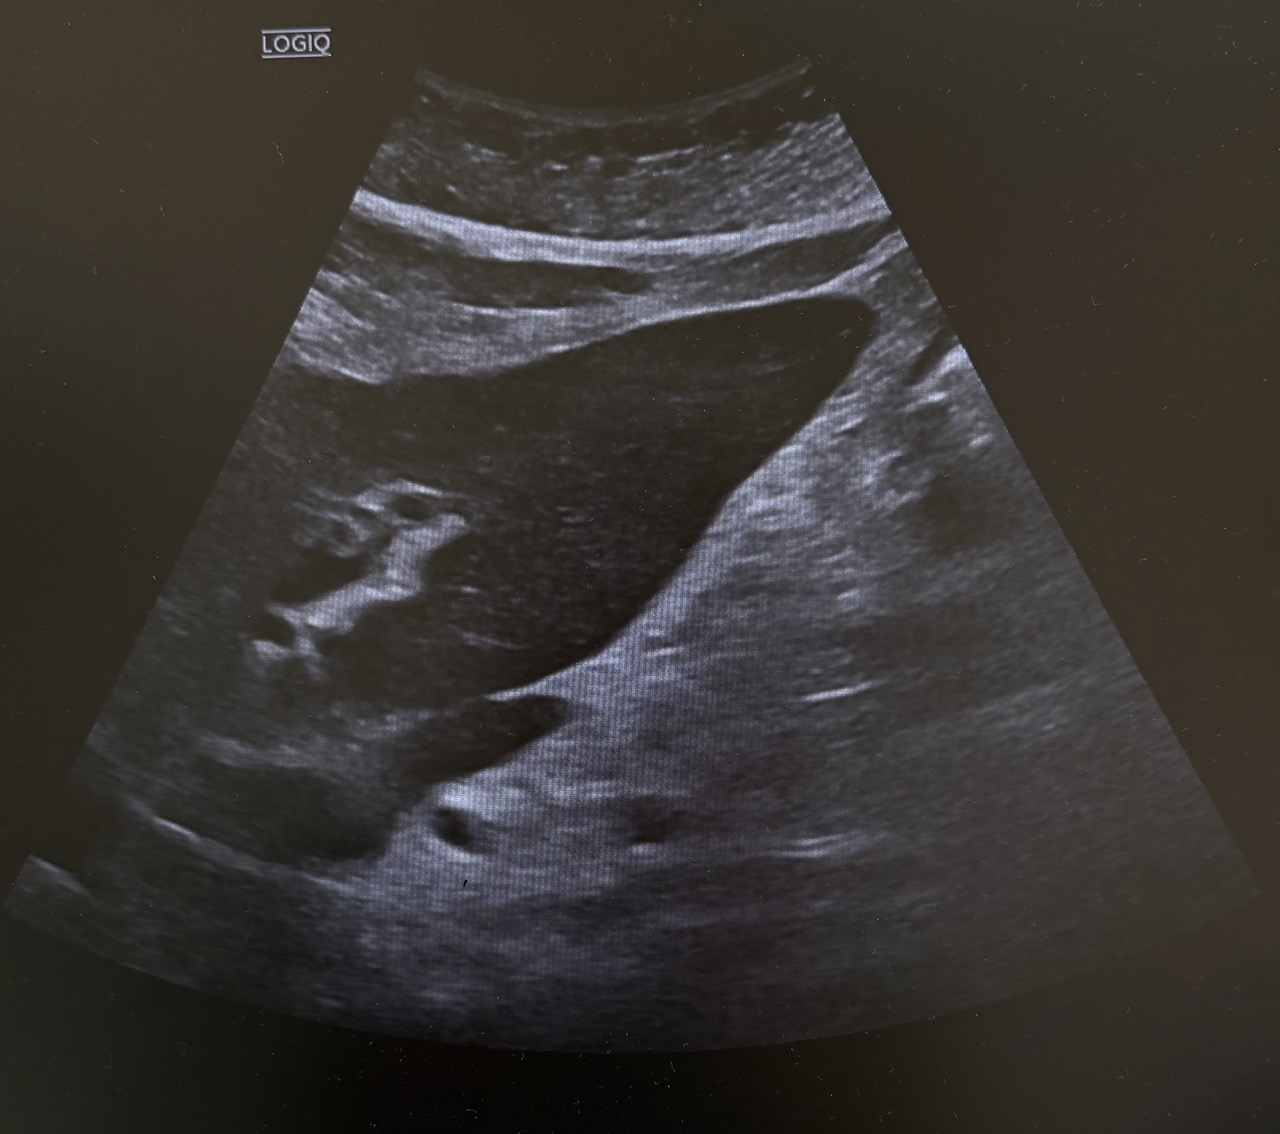

Ecografía en el centro de salud: Vesícula biliar con presencia de litiasis en su interior, distendida y engrosada. Murphy ecográfico positivo.

Desde el centro de salud, con la exploración y los hallazgos de ecografía nos orientó a colecistitis aguda litiásica por lo que se decidió traslado a urgencias para realización de analítica, ecografía por radiólogo y valoración por cirugía general.

La analítica junto con ecografía de urgencias coincidió con hallazgos observados en la ecografía del centro de salud, confirmando así colecistitis aguda evolucionada.